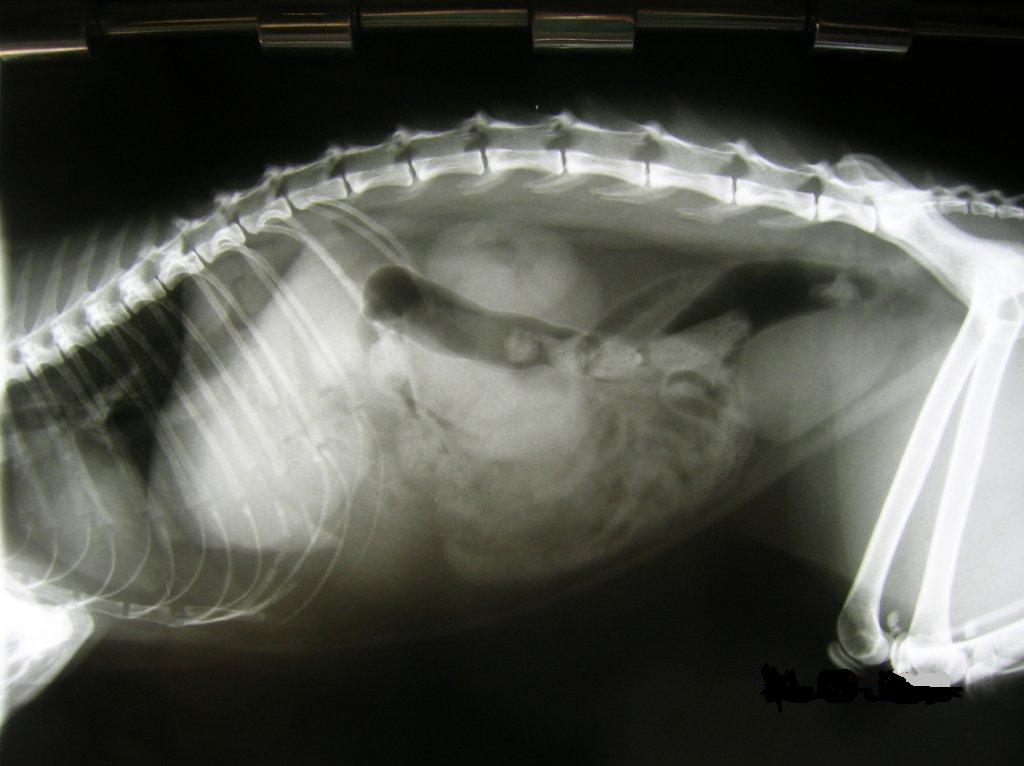

L'esame radiografico permette di visualizzare non solo problemi osteoarticolari, ma anche di avere basilari informazioni sugli organi interni addominali: valutandone densità, forma, posizione, rapporto con gli altri visceri, stato di ripienezza e tipo di contenuto se organi cavi; informazioni ulteriormente importanti si hanno nel distretto toracico, per quanto attiene in particolare a vasi, cuore, mediastino e distretto polmonare. Può essere integrato con l'utilizzo di pasto baritato quale mezzo di contrasto per meglio evidenziare lo stato in essere dell'apparato digerente. Importante è poi l'uso della radiologia per l'esame di ogni altro distretto anatomico: in dentistica permette per esempio di esaminare i rapporti tra osso e radici dentarie, evidenziando ciò che non è visibile esternamente, alla sola visita (ascessi, piorrea, anchilosi, etc.). Se necessario, può integrarsi validamente con l'esame ecografico per fornire ulteriori informazioni. Spesso i raggi vedono ciò che all'ecografia è silente e viceversa, in un processo di reciproca sinergia.

Nella mia struttura, dotata di acquisitore di immagini Fuji, viene effettuata una processazione elettronica dell'immagine radiografica, permettendo di ruotare, invertire e mutare contrasto e tonalità, effettuare misurazioni, nonché ingrandire fini particolari; onde ottimizzare l'ottenimento di immagini il più possibile dettagliate, quindi diagnostiche, anche su pazienti di piccole dimensioni (cuccioli, conigli nani, furetti, etc.)